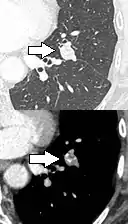

FDG-PET study of a 71-year-old woman with a solitary pulmonary nodule (thin arrow) in the left lower lobe near the heart. The scan also revealed abnormal increased activity at the gastro-esophageal junction (thick arrow). The final diagnosis was non-Hodgkin lymphoma at both sites.

If there is an intermediate risk of malignancy, further imaging with positron emission tomography (PET scan) is appropriate (if available). It can be done simultaneously as a CT scan in the form of PET-CT. Around 95% of patients with a malignant nodule will have an abnormal PET scan, while around 78% of patients with a benign nodule will look normal on PET (this is the test sensitivity and specificity).[15] Thus, an abnormal PET scan will reliably pick up cancer, but several other types of nodules (inflammatory or infectious, for example) will also show up on a PET scan. If the nodule has a diameter of less than one centimeter, PET scans are often avoided because of an increased risk of falsely normal results.[15][16][17] Cancerous lesions usually have a high metabolism on PET, as demonstrated by their high uptake of FDG (a radioactive sugar).